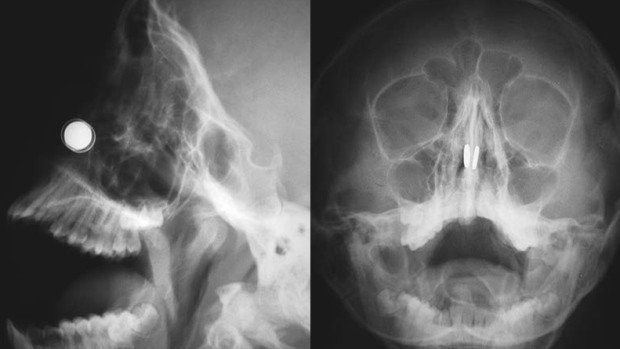

Konuyla ilgili açıklamalarda bulunan Yakın Doğu Üniversitesi Hastanesi’nde Doç. Dr. Kadir Çağdaş Kazıkdaş, en güçlü mıknatıslardan olan neodyum mıknatıslarının buruna girer girmez çocuğun burun direği etrafında birbirine yapıştığını açıkladı. Çocuğun mıknatısları burnuna soktuktan yaklaşık altı saat sonra dayanılmaz bir ağrı, burun kanaması ve burun içinde kabuklanma şikayetleri ile hastanenin acil servisine getirildiğini ifade eden Doç. Dr. Kazıkdaş, yapılan ilk müdahalede mıknatısların halen çocuğun burnunda olup olmadığının kesin olarak anlaşılamadığını, burun içerisinde de kanamaya bağlı çok fazla kabuklanma olduğunu, bu arada çocuğun duyduğu ağrı ve korku nedeniyle doktorların müdahale girişimlerini de engellediğini söyledi. Doç. Dr. Kazıkdaş daha sonra hastanın Kulak, Burun Boğaz Polikliniği’ne sevk edilerek, yüz röntgeninin çekildiğini, böylece burun içerisinde birbirine kenetlenmiş olan mıknatısların tespit edilebildiğini söyledi.

Geleneksel cerrahi aletlerle mıknatısları çıkarmayı denediklerini ama bu şekilde sonuç alamadıklarını ifade eden Doç. Dr. Kadir Çağdaş Kazıkdaş, son olarak burun içinde kenetlenmiş olan mıknatısları kaldırıp çıkarmak için burun dışından sıradan mıknatıslar kullanmayı düşündüklerini ifade ederek şöyle devam etti; “Bu yöntem ile sol taraftaki mıknatısı kolaylıkla çıkarmayı başardık. Ardından ikinci mıknatısı çıkarmak da saniyeler sürdü. Çocuğun burun kıkırdağında oluşan hasarlı bölgeye ve travmatize olan dokulara yapay yama uygulandı. İlerleyen dönemdeki iyileşmeyi desteklemesi için silikon burun ateli de takıldı. Atel operasyon sonrasında on gün boyunca hastanın burnunda takılı kaldı.”